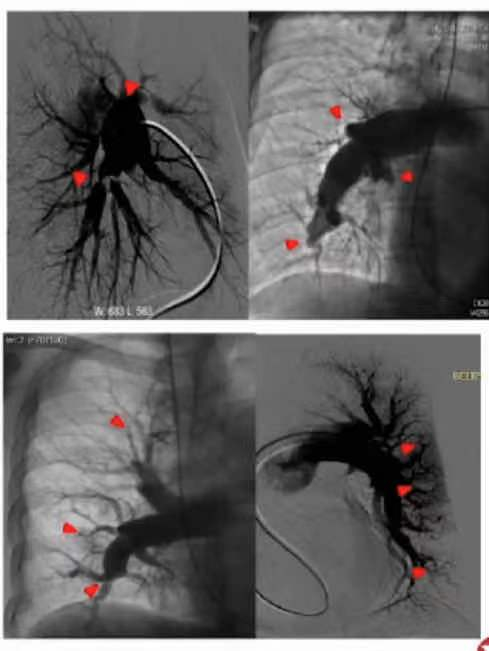

3.金标准:右心导管+肺动脉造影

典型表现:囊样病变,网状或带状伴随/不伴随狭窄后扩张,血管壁不规整,突然变细,节段闭塞。

图 肺动脉造影